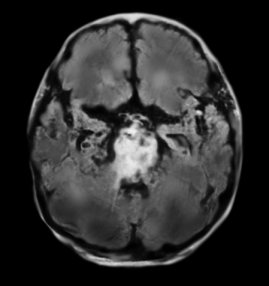

감금증후군 뇌 MRI: 교뇌를 전반적으로 침범한 뇌경색

락트-인 증후군(감금증후군)은 의식은 있지만 전신마비로 인하여 외부자극에 반응하지 못하는 상태이다. 환자가 자발적인 움직임을 보이지 않고 말을 하지 않기 때문에 외관상 혼수상태로 잘못 판단할 수 있지만, 혼수상태와 달리 락트-인 증후군에서는 각성이 유지되어 있고 단지 운동기능만 차단되어 있다. 뇌간(숨뇌, 뇌줄기)은 척수와 대뇌 사이에 위치하고 있어 뇌에서 나오는 운동신경을 척수로 이어주는 역할을 한다. 운동신경은 뇌간 중 다리뇌(교뇌)에서 가장 앞쪽을 지나가는데, 이 부분에서 양쪽 운동신경이 모두 손상을 받으면 얼굴을 포함하여 팔다리를 움직이지 못하게 된다. 그러나 이 경우 중간뇌(중뇌)는 손상되지 않았기 때문에 눈을 뜨거나 수직 방향으로 안구를 움직이는 것은 가능하다. 따라서 일부 환자들은 눈을 뜨고 감는 방법으로 다른 사람과 의사소통을 했다는 보고가 있다. 또한 락트-인 증후군 환자는 각성에 관여하는 기관 및 감각신경은 정상이기 때문에 신체감각 및 청각 자극이 대뇌로 전달될 수 있다.